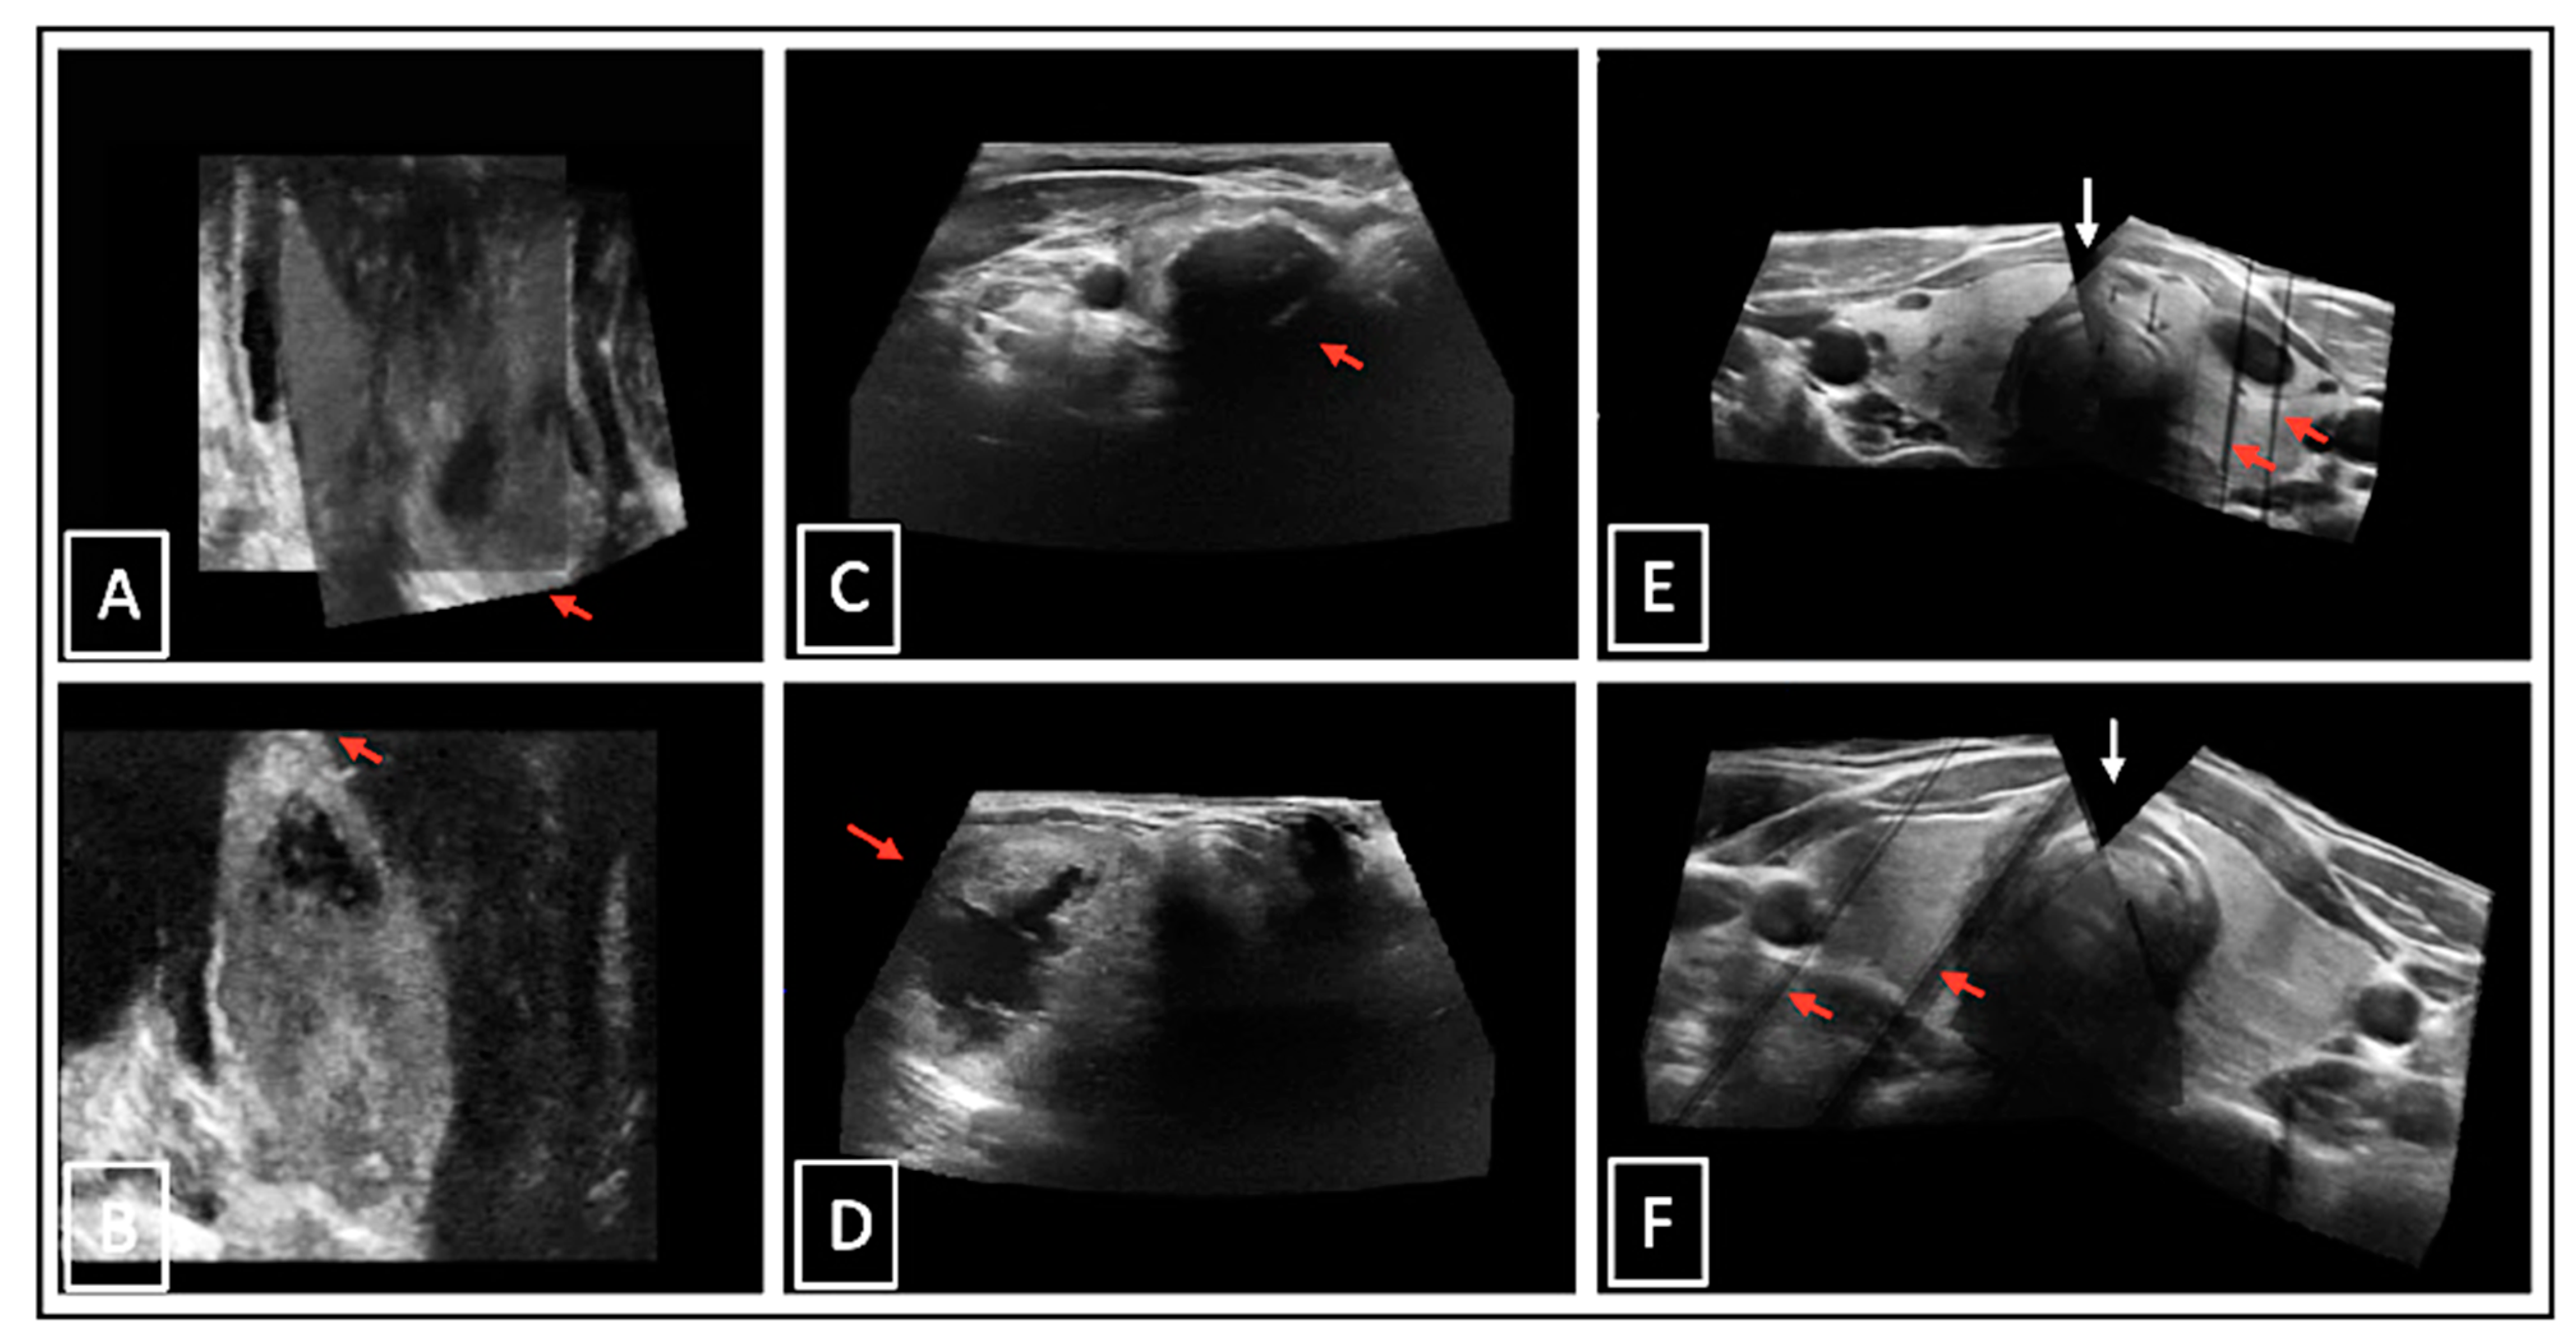

Figure 7.

Examples of suboptimal 3D-US images: incompletely captured thyroid pols on 3DmsUS in coronal plane ((A,B), red arrows); incompletely displayed thyroid tissue due to dorsal acoustic deletions behind calcifications ((C), red arrow) and a large nodule ((D), red arrow) in transverse plane; incompletely displayed isthmus ((E,F), white arrows) and artefacts due to too-fast moved US probe while 3D scan acquisition ((E,F), red arrows).

In cases of 3DsnUS, the examiner had to pay attention to a constant probe movement speed in order to avoid artefacts. From the patient’s side, these could be reduced by a breath-holding technique. Motion artefacts made the stitching process and the application of the MC method more difficult and could lead to measurement inaccuracies. In theory, electromagnetic interferences from metal, mains, or LAN voltage fields are possible, but has not been observed in our examinations.

For accurate 3DmsUS results, constant orthograde fixation of the probe on the neck surface was necessary. An important prerequisite was the estimation of the correct probe position in order to be able to capture the entire thyroid lobe, restricted by a maximum angle of 84°. Incompletely captured lobes needed to be avoided. In nearly all cases repetitive attempts very necessary. The acquisition parameters for 3D-US were individually optimized and, therefore, examiner-dependent, resulting in variable image quality.